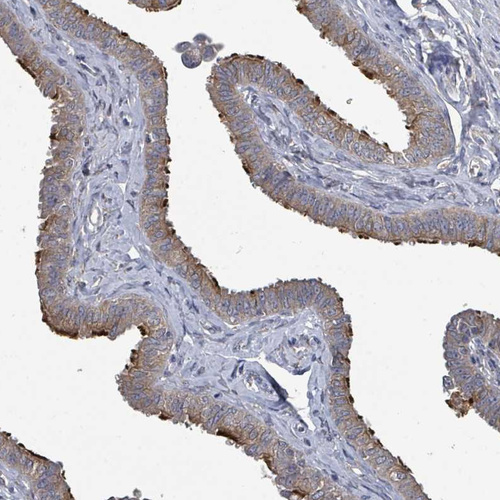

Immunohistochemical staining of human kidney shows moderate cytoplasmic positivity in cells in tubules.